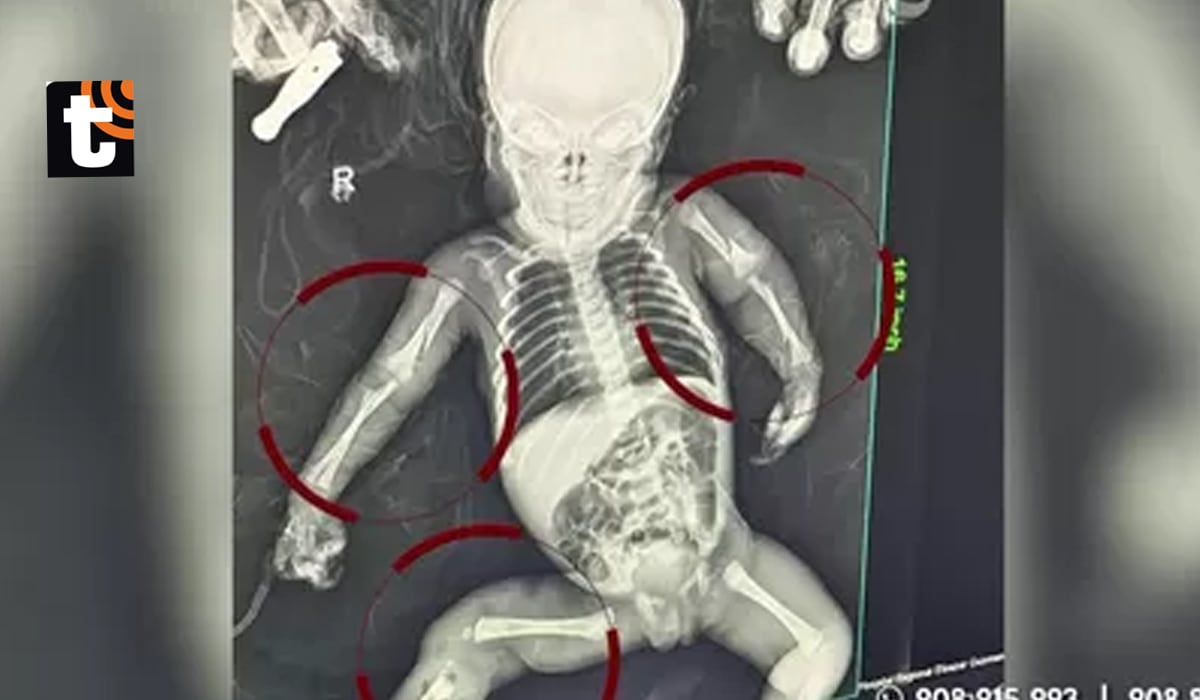

Tras los exámenes médicos realizados, se confirmó que la menor presentaba fracturas en ambos brazos y en una de sus piernas. La gravedad de las lesiones permitió a los médicos descartar un accidente doméstico, por lo que se dio aviso inmediato a la Policía Nacional.

Debido a la complejidad de las fracturas, los médicos determinaron que la bebé necesitaba atención especializada. Por ello, fue trasladada de emergencia desde Chimbote hacia un hospital de mayor complejidad en la ciudad de Lima.